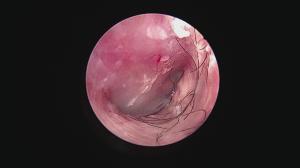

鉗子では、鼓膜を傷つけてしまうため、カテーテルにて洗浄します

細いカテーテルを挿入し、耳垢を丁寧に除去

鼓膜が見えました!

作業時間は約1時間・・。

細かい作業なので結構神経使いますね。

きれいになることを確認できた時、とっても達成感があります。

その後は期待通り、経過も順調で飼い主さんも満足していただけました。

鉗子では、鼓膜を傷つけてしまうため、カテーテルにて洗浄します

細いカテーテルを挿入し、耳垢を丁寧に除去

鼓膜が見えました!

作業時間は約1時間・・。

細かい作業なので結構神経使いますね。

きれいになることを確認できた時、とっても達成感があります。

その後は期待通り、経過も順調で飼い主さんも満足していただけました。